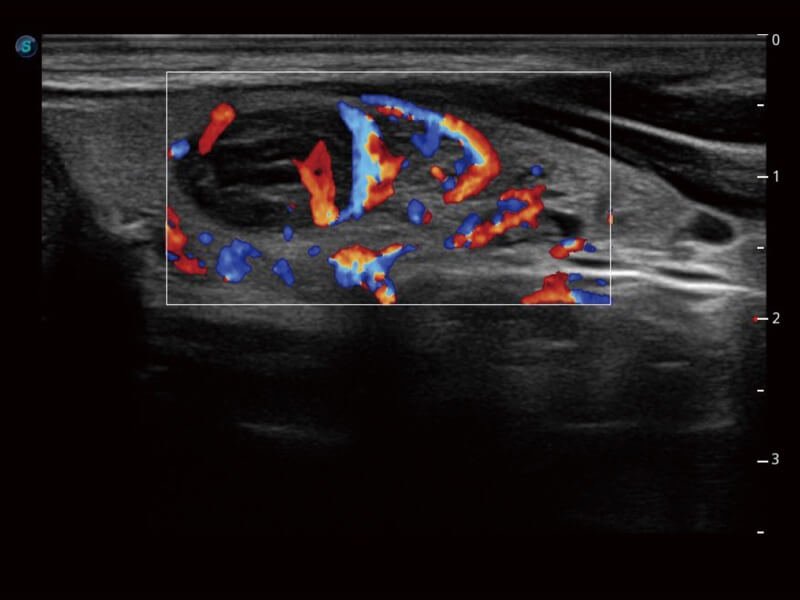

SR-Flow

The separation of blood flow and tissue signal becomes more easily with SR-Flow given the use of a highly effective filter technology. It enables a dynamic and vivid Doppler display with high sensitivity while ensuring a realistic evidence for detection of slow flows.

Micro F

Micro F provides an innovative method to expand the range of visible flow in ultrasound, especially for visualizing hemodynamic for tiny vessels. Detailed views of blood flow in relation to nearby tissue also render more diagnostic confidence to evaluate lesions and tumors.